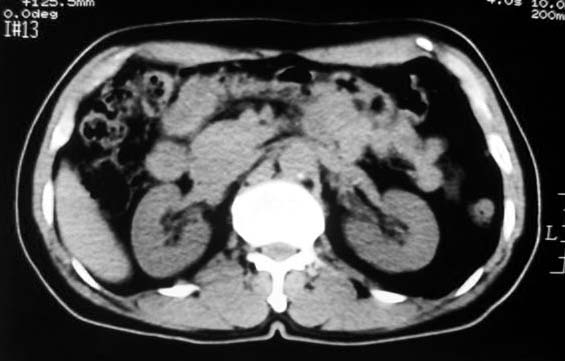

定位:病灶位于胃腔外,大弯侧后下方.

特征:实质性肿物,边界清楚,内见低密度影,明显压迫胃壁,并形成切迹.

考虑:脾门淋巴瘤或间质瘤.

胃大弯侧,胃底与胃体交界处可见一圆形软组织肿块影,边缘较光整,内部密度较均匀

考虑:脾门淋巴瘤或间质瘤

考虑:胃间质瘤?息肉?

病灶起源于胃壁向腔内外突出,边缘光整,内可见片状低密度区,考虑胃壁非上皮性肿瘤可能性大

病灶起源于胃壁向腔内外突出,边缘光整,内可见片状低密度区,考虑间质瘤可能性大,建议增强扫描。